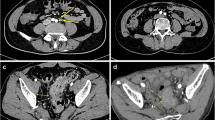

Radiologic–pathologic node-by-node comparison

All rectal MRI images of patients with rectal cancer were analyzed preoperatively by a radiologist with more than 15 years of experience interpreting rectal imaging studies. MRI high-resolution oblique-axis T2-weighted imaging and DW images were used as evaluation sequences. Similar to the method described in previous reports [18,19,20], after referencing DWI, the radiologist performed anatomic correlation matching with T2WI to confirm regional LNs and recorded the nodal size, nodal location, and level sequence of each LN. All LNs evaluated by imaging were drawn on anatomical maps to obtain accurate histology-imaging correlation node by node (Fig. 1). All patients underwent total mesorectal excision (TME) within 2 weeks of the imaging examination. Fresh specimens were pinned to a foam board, sent to the pathology laboratory for macroscopic examination, and then immersed in formalin saline for at least 72 h for fixation. A pathologist with 15 years of experience guided each specimen by a 3 mm ruled template and sectioned at 3 mm intervals transversely, perpendicular to the long axis of the mesorectum, from the distal aspect to the proximal aspect. All slices were numbered and photographed. LNs were carefully identified on each slice, and the anatomical map was used as a template for node-by-node correspondence. All matched LNs were numbered and placed in individual trays for processing. In subsequent microscopy, all slides were stained with hematoxylin and eosin. The benign and malignant LNs were reported according to the microscopy results.

For evaluation on a node-by-node basis, only those LNs that could be identified were included. A total of 532 LNs were identified during imaging evaluation. Of these, 500 were confirmed on histopathological findings. Conversely, only 500/1377 (36%) nodes harvested from the mesorectum on histopathological examination could be matched to nodes on imaging evaluation (Fig. 2). Among the 500 matched nodes, 353 did not receive neoadjuvant therapy. A total of 147 received neoadjuvant therapy. The 500 matched LNs were randomly allocated to a training cohort and a validation cohort in a ratio of 7:3.